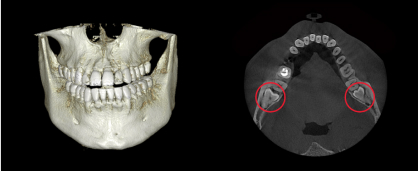

img-0501-4-1.png

사랑니 발치 전

CT를 촬영하는 이유.

#정밀한 스캐닝 #낮은 방사선량

#오차 최소화

파노라마는 평면의 2차원적인 사진이고 치과용 CT는 3차원적인

사진으로 CT를 통해 사랑니의 매복 상태, 사랑니 뿌리와 신경의 위치

관계 등을 자세히 파악할 수 있습니다.

img-0501-4-2.jpg img-0501-4-3.png